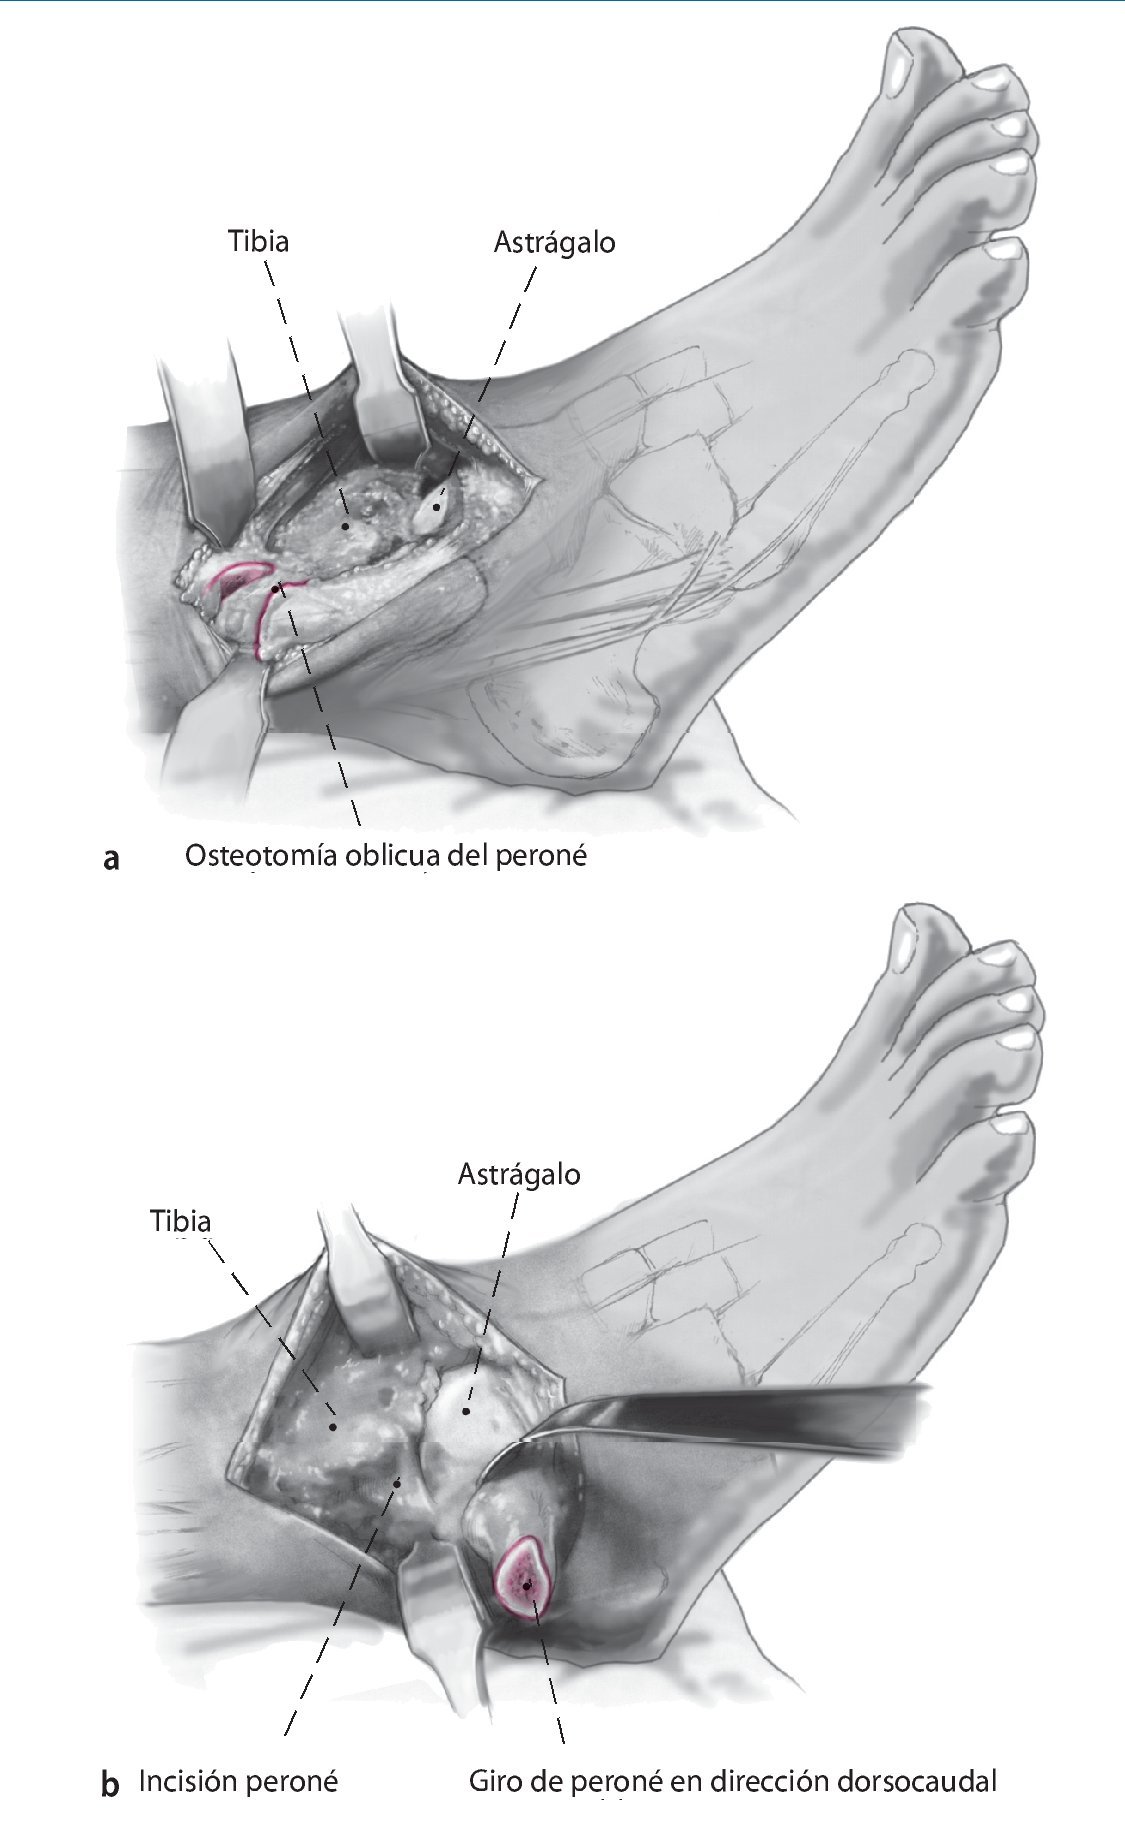

Fig. 4 En el ángulo posterolateral se realiza incisión en la vaina tendinosa peronea. Colocar los separadores de Hohmann como protección en posición anterior y posterior del peroné. Realizar osteotomía oblicua del peroné (a) usando la sierra oscilante a unos 6 cm por encima del espacio articular. Se reseca una sección de 8 mm para facilitar la compresión apropiada al final del procedimiento. Gire el peroné en dirección dorsocaudal (b).

Fig. 5 Decortización de la cara medial del peroné distal con sierra oscilante. Esto aumenta la potencia biológica de la refijación.